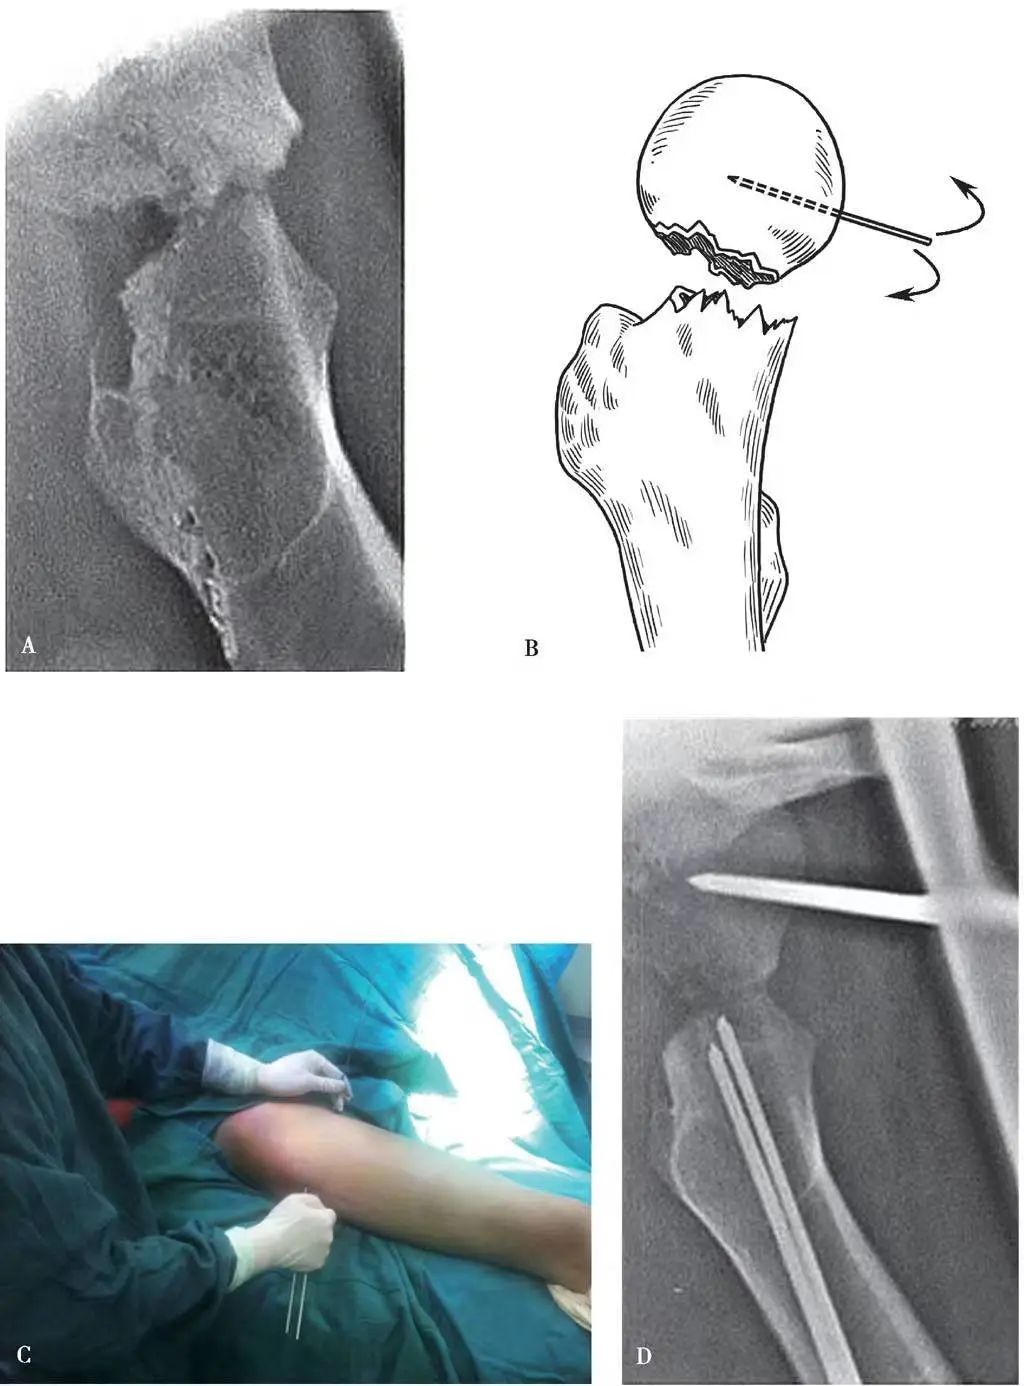

Si le repositionnement n'est pas réalisé par les méthodes ci-dessus, cela indique généralement soit que la tête fémorale a été cassée ou qu'il y a eu une séparation en rotation entre la tête et le cou (Figure 1A), ou qu'il y a une insertion quelque part entre la tête et cou.(Cela peut se produire dans n'importe lequel des types Garden II, III ou IV).Dans ce cas, la rotation du membre affecté pour aligner la fracture de la tête et du cou n'est plus efficace.Afin d'éviter l'incision et le repositionnement, une technique de levier percutané à l'aiguille peut être utilisée pour repositionner la fracture.

Une aiguille circulaire en os de 3,0 à 3,5 mm de diamètre est insérée verticalement à travers la peau 1 à 2 cm sous la jonction du ligament inguinal et de l'artère fémorale à l'avant de la tête fémorale, et l'aiguille est tournée plus profondément vers le centre de la tête fémorale sous la supervision de la machine C-bras (figure 1B).

Pour renforcer la force de levier, une deuxième aiguille circulaire osseuse peut être insérée à 4-5 mm parallèlement à cette aiguille, avec l'extrémité de l'aiguille laissée à l'extérieur de la peau.

A travers le grand trochanter, deux aiguilles circulaires à os de 3,5 mm de diamètre sont forées par voie percutanée selon l'angle de la tige cervicale et l'angle d'inclinaison antérieure, atteignant l'extrémité distale de la fracture du col fémoral (ne pas traverser la fracture) et laissant l'extrémité de l'aiguille à l'extérieur de la peau.

L'opérateur tient les deux ensembles de queues d'aiguille avec les deux mains et ajuste les sections de fracture de la tête et du cou pour s'aligner les unes avec les autres avec la coopération de l'assistant (figure 1C-E).

Une fois l'alignement satisfaisant, une broche ronde osseuse insérée au niveau du grand trochanter est vissée dans la tête fémorale pour une fixation temporaire, et plusieurs vis creuses sont ensuite insérées dans la tête fémorale (figure 1F).

Figure 1 Fracture du col fémoral repositionnée par levier percutané à l'aiguille